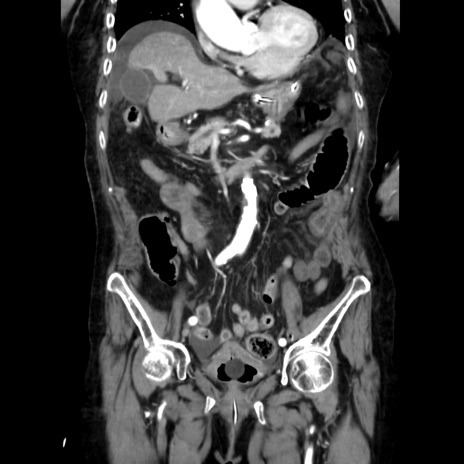

症例40(冠状断像)

【症例】90歳代女性

【主訴】腹痛・嘔吐

【現病歴】 食欲低下、嘔吐があり昨日他院受診。肺炎と診断され入院となる。入院後より腹部全体に圧痛あり。胃管留置され経過みていたが、症状持続するため、

当院転院となる。

【既往歴】胸椎圧迫骨折、胆石症

【身体所見】腹部:中央に激痛あり、圧痛あり、反跳痛不明

【データ】WBC 17100、CRP 18.82

冠状断像